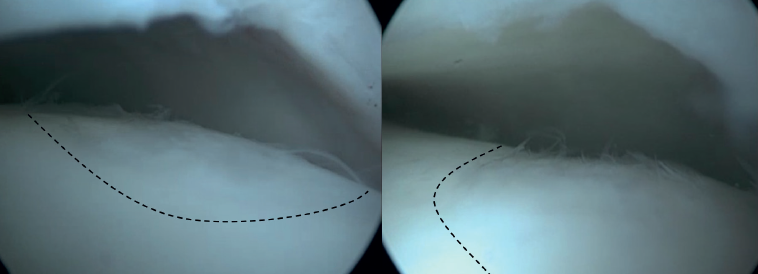

Arthroscopic Bone Marrow Stimulation (BMS) is the most frequently used treatment for primary OLT(22). BMS can be deployed for relatively smaller (<15 mm), non-cystic, non-fixable lesions(20,23). Arthroscopic BMS starts with debridement and curettage of the defective cartilage and subchondral bone(24). Subsequently, drilling or perforation of the sclerotic bone at the base of the defect is performed, often using a Kirschner wire or microfracture awl(25). The holes should be made to a depth that results in bleeding of the subchondral bone or the presence of fat droplets(23) (Figure 4). This technique disrupts the intraosseous blood vessels, leading to the subchondral bone bleeding and the formation of a fibrin clot. The release of mesenchymal blood cells promotes vascularization which induces the formation of fibrocartilage(26). When an isolated (i.e., no other damage to bone/within the joint) cartilage lesion with a macroscopically intact subchondral bone layer, is present, debridement only can be performed(27).